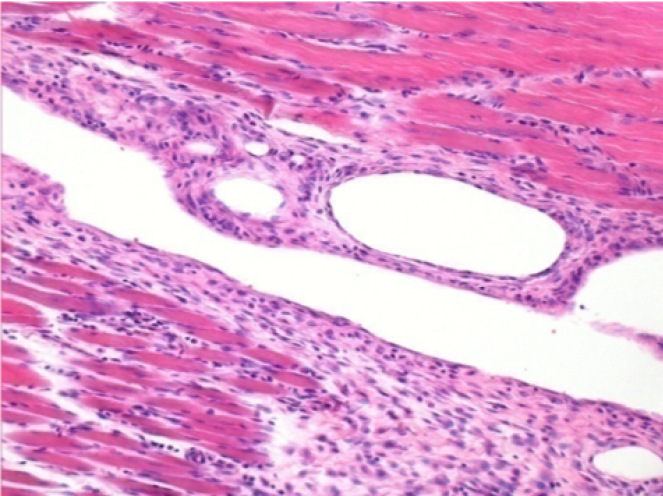

10 días después de la inyección de Endopeel

10 días después de la inyección de Endopeel 0,1 ml en el músculo pretibial derecho.

Aquí puede ver la formación de las vacuolas que están rodeadas de linfocitos. Las vacuolas son diferentes a la necrosis tisular. La presencia de linfocitos está relacionada con la permeabilidad de las membranas celulares.

L : Control-100xD10

R:100xD10

R :200xD10

R :400xD10